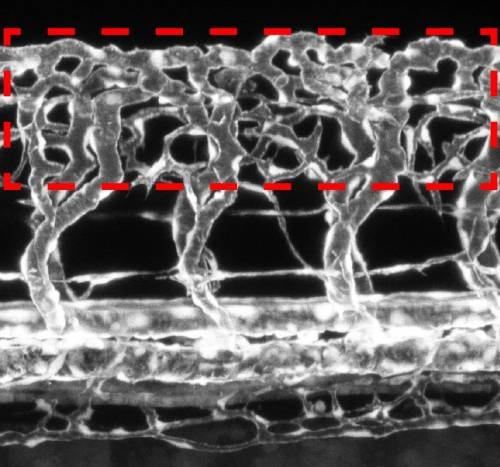

Una red vascular hiperramificada rodeando la médula espinal (la zona dentro del rectángulo conformado por las cuatro líneas discontinuas rojas) de un embrión de pez cebra. Los vasos sanguíneos se muestran de color blanco. (Imagen: Le Noble / KIT)